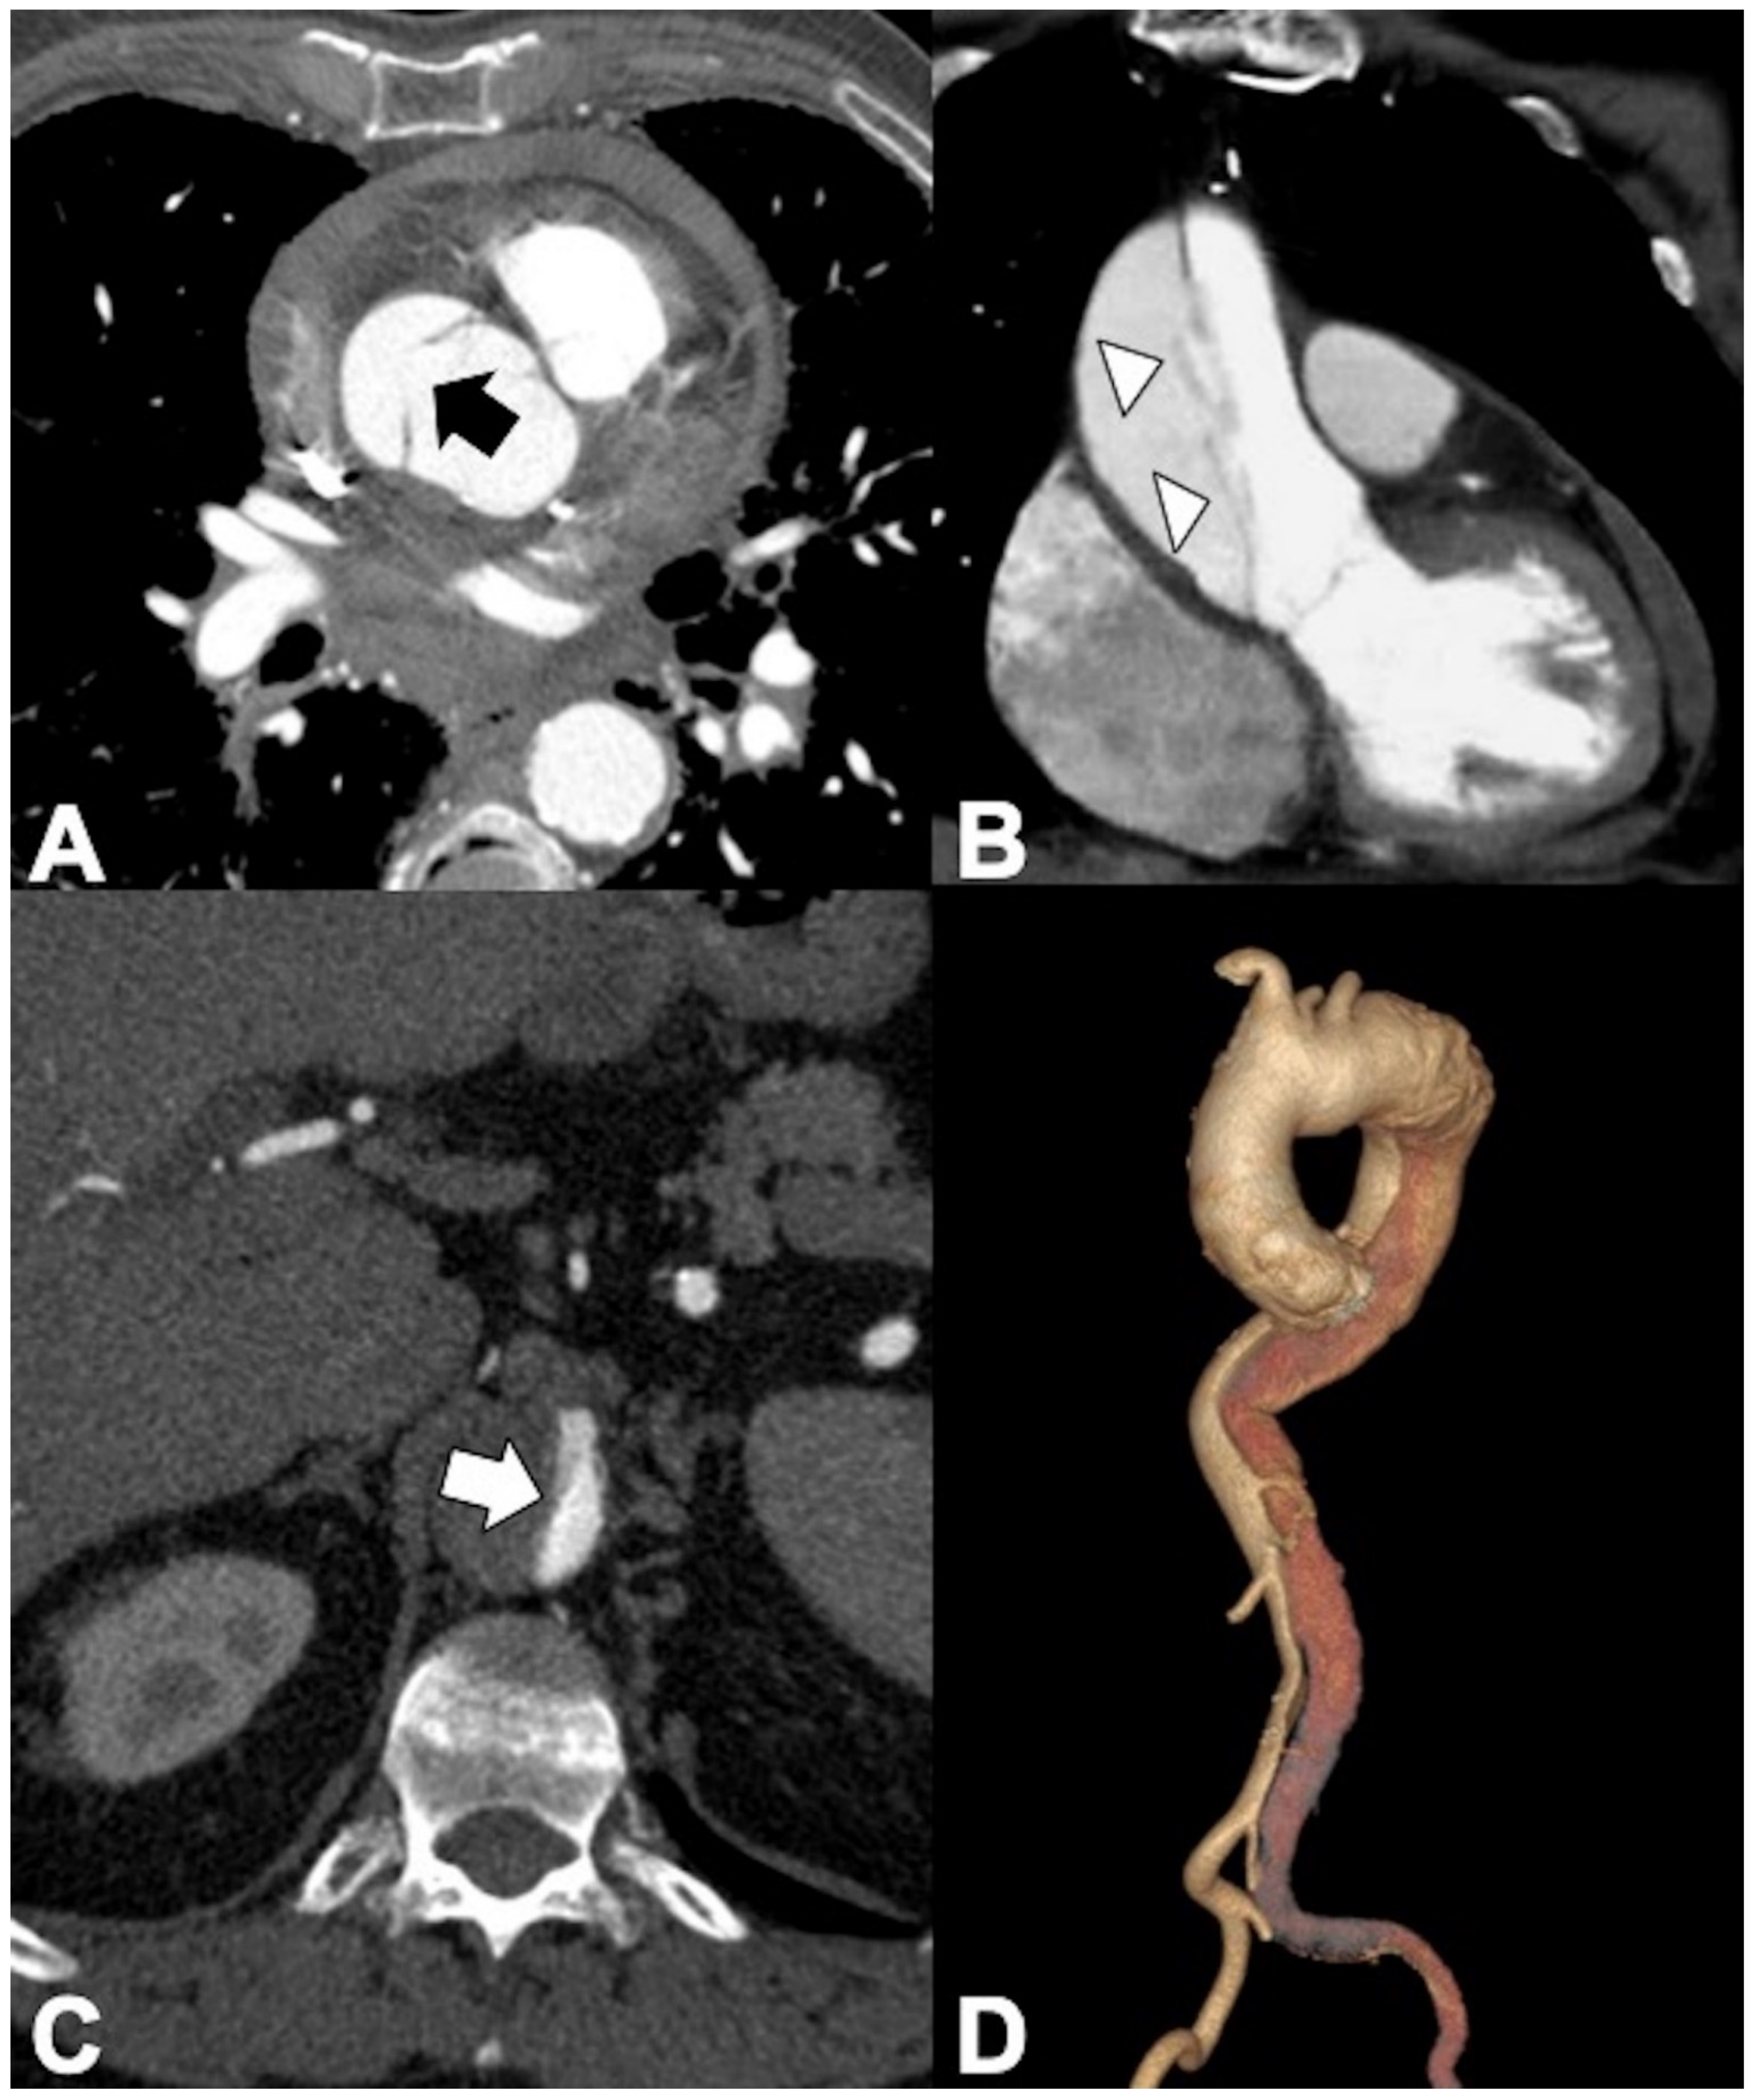

AD (70% of AAS) arises from a tear in the aortic intima (primary or most proximal entry tear) exposing the medial layer to the pulsatile blood flow. CTA intimomedial rupture sign enables direct visualization of the intimomedial rupture indicating direction of the intimomedial entrance tear from true (TL) to false lumen (FL) in systole. However, the direction can be bidirectional or reversed depending on the cardiac phase (Figure 5A) [34].

Figure 5. CTA findings in aortic dissection. (A) Axial CTA image showing intimomedial rupture sign in the ascending aorta (arrow) in type A dissection, indicating direction of the intimomedial entrance tear from true to false lumen. (B) Coronal CTA MPR image showing the intimomedial flap travelling parallel to the aorta long axis. Note the cobweb sign by thin, string-like filaments of the media layer in the false lumen (arrowheads). (C) Axial CTA image shows pressure competition between lumina and opacified true lumen collapse (arrow). (D) The different density of the TL (more intensely opacified due to faster flow) and FL in the early angiographic phase allows them to be clearly distinguished in the coronal VR reconstruction.

The most proximal tear usually occurs at a point of high shear force in systole (lateral right wall of ascending aorta, distal to LSA in the DTA). The progressive separation of the aortic wall layers results in the formation of a FL within the media having pressures ≥ those in the TL, which travels parallel to the aorta long axis (Figure 5B) [21,24,25,35]. The inner layer of the media remains contiguous with the aortic intima, creating an intimomedial flap, readily seen on cross-sectional imaging [21,24,25,36,37].

The outer portion of the media remains attached to the adventitial layer, creating the thin weak outer wall of the FL that dilates. The greater the proportion of the media involved in the flap, the thinner the external wall of the FL, and therefore, the higher the risk of adventitial disruption and aortic rupture [36,37,38]. The dissections may remain patent as a false lumen, thrombose, recommunicate with the true lumen through fenestrations (re-entry tears), or rupture into potential spaces such as the pericardial, pleural, or peritoneal cavities. Aortic rupture quickly leads to exsanguination and death. The overall degree of dilation of the FL depends on the blood pressure, the residual wall thickness, and the percentage of wall circumference involved in the dissection. One or more re-entry communications between lumina allow blood redirection into the TL and free blood circulation between lumina. Progressive pressurization of the FL resulting in TL collapse is highly variable based on the number of tears between the lumina, the chronicity of the flap, and the degree of control of the patient’s blood pressure (Figure 5C) [36,37,38]. Conversely, the FL may also end blindly in a cul-de-sac, creating a blood clot. Differentiation between TL and FL is important in the planning of percutaneous treatment with endovascular grafts or surgical repair of aortic dissections [39]. The main CTA findings that differentiate TL and FL are listed in Table 4 (Figure 5D) [36,37,38,39]. The beak sign occurs at the acute angle of the intimomedial flap and outer wall of the FL (Figure 6A) [40]; the cobweb sign represents strands or ribbons of media crossing the FL and appearing as thin filiform filling defects [39,41]. Calcification may help to differentiate between the FL and TL—it has been described as only being seen in the wall of TL [25,37]. The FL (and the flap) can propagate distally toward the aortic bifurcation and retrograde toward the aortic root (Figure 6B).